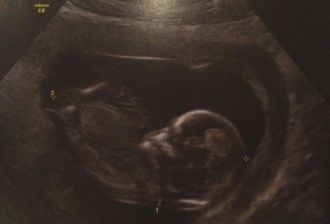

Aujourd'hui nous sommes le 13 Février 2013, et avons rendez-vous à l’hôpital avec un Mr le gynécologue qui va déterminer la taille de ta nuque avec une machine beaucoup plus perfectionnée que la précédente.

Énorme satisfaction en voyant la netteté des images échographiques, il n'y a pas à dire la technologie, quelle merveilleuse évolution !!

Nous pouvons voir à travers l'écran, ton joli profil ( toujours la même sensation lorsque je te vois à l'écran, indéfinissable ), mr le gynécologue nous montre tes pieds, ton cerveau et nous fait entendre ton cœur qui bat à une et mille vitesse...

Il mesure tu nuque qui est forcément minuscule (1.34mm ) et nous rassure sur l'épaisseur ( manque plus qu'à faire la prise de sang pour vérifier l'analyse trisomie 21 ) mais normalement il n'y a pas de risque... ( RQ : sait on jamais ).

La question qui nous vient à l'esprit : " mais est ce que c'est il ou elle " ??!!

Papa veut savoir mais maman allongée sur le fauteuil d’examen hésite au dernier moment... donc nous nous mettons d'accord tous les 3 ( mr le gynécologue, papa et moi ), à la fin du rendez-vous, maman sortira de la pièce et le médecin le dira à ton papa...

Papa ne pouvant pas garder de secret et est tellement démonstratif qu'il n'a pas pu cacher sa joie...

MAMAN a deviné : tu seras un petit garçon :)